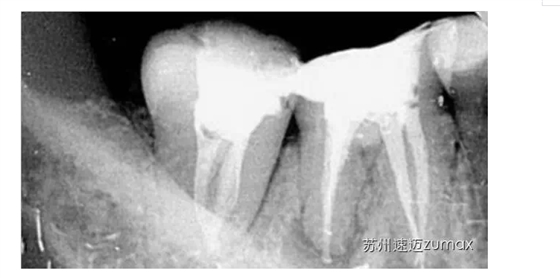

C形根管的治療最好是在手術顯微鏡下進行。上橡皮障后開髓,去除髓室中的牙髓組織,使用DG16仔細探查根管口位置,然后用10或15號不銹鋼K銼探查根管的形態(tài)、直徑和走向。當根管口呈連續(xù)的C形時,插入根管內的診斷銼為2~4個,通常為3個。當根管口呈分號形時,可以在較小的根管內插入1個診斷銼,在較大的根管內插入1~3個診斷銼。